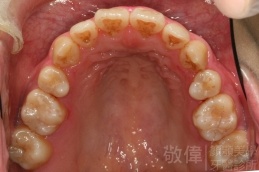

變臉矯正,原來戽斗妹跟大歪臉變成自信正妹

經由本院3D數影X光影像儀分析、與3D齒顎顏矯正技術,再配合口腔顎面正顎專科醫師施以正顎手術治療,雙方共同合作,使患者臉部外觀有很好的改善,大歪變小歪,產生了天南地北的大改變,她的人生也整個變得不一樣。

因為矯正與正顎手術的配合,使「戽斗妹」變成了「陽光正妹」,完全的改變了她的人生,在面對各種場合、與人交際都散發出自信微笑。所以,奉勸家長,如果小朋友有臉顎畸型的問題,應該考慮配合做這種簡單、安全、有效的正顎手術。